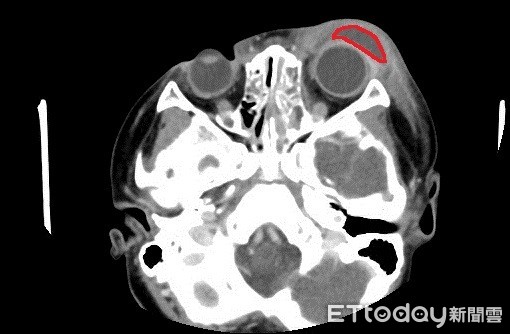

▲男童的電腦斷層顯示,紅圈處出現眼睛潰傷、紅腫症狀。(圖/亞洲大學附屬醫院提供)

亞洲大學附屬醫院兒科部主治醫師陳劍韜表示,廖小弟流黃鼻水症狀已持續2至3天,這次伴隨單側眼睛異常紅腫,與一般過敏是雙側眼睛紅腫不同,經電腦斷層檢查,確診為急性鼻竇炎合併嚴重眼眶周圍膿瘍,因擔心影響視力,便由眼科醫師進行眼科手術,引流膿瘍。

台中3歲廖小弟因左眼及臉頰紅腫,合併黃膿鼻涕、發燒不退,赴醫確診為急性鼻竇炎合併眼周感染,因紅腫相當嚴重,兒科醫師擔心眼睛感染恐影響視神經,透過電腦斷層檢查後,發現眼皮內已化膿,旋即會診眼科,以手術引流膿液及施打抗生素,兩周後健康出院,醫師也提醒若輕忽病症,恐有失明風險。